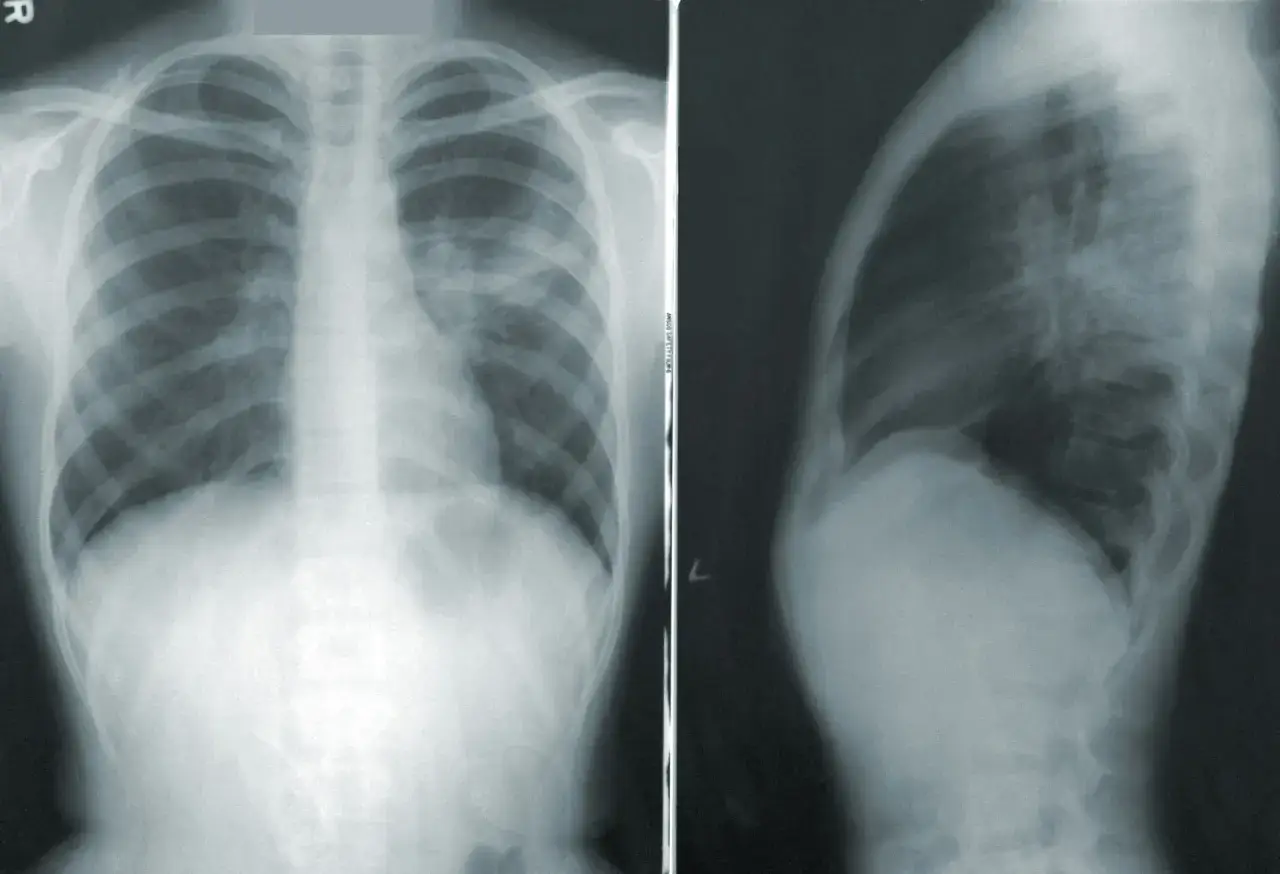

Czym tak naprawdę jest "pęknięte płuco", czyli odma w prostych słowach

Często słyszymy potoczne określenie "pęknięte płuco", jednak medycznie bardziej precyzyjne jest mówienie o "zapadniętym płucu". Odma płucna to nic innego jak nagromadzenie powietrza w jamie opłucnej, czyli przestrzeni między płucem a wewnętrzną ścianą klatki piersiowej. To właśnie to powietrze powoduje ucisk na płuco, prowadząc do jego częściowego lub całkowitego zapadnięcia.

Jak działa płuco i co się dzieje, gdy do opłucnej dostaje się powietrze?

Nasze płuca są otoczone dwiema błonami – opłucną płucną i opłucną ścienną. Między nimi znajduje się niewielka przestrzeń, zwana jamą opłucnej, w której panuje ujemne ciśnienie. To ujemne ciśnienie jest kluczowe, ponieważ dzięki niemu płuco może swobodnie rozprężać się i kurczyć podczas oddychania. Kiedy jednak do tej przestrzeni dostanie się powietrze – czy to z uszkodzonego płuca, czy z zewnątrz przez uraz – ujemne ciśnienie zanika. Powietrze zaczyna uciskać płuco, powodując jego zapadnięcie. Im więcej powietrza się zgromadzi, tym bardziej płuco się kurczy, co uniemożliwia jego prawidłowe funkcjonowanie.